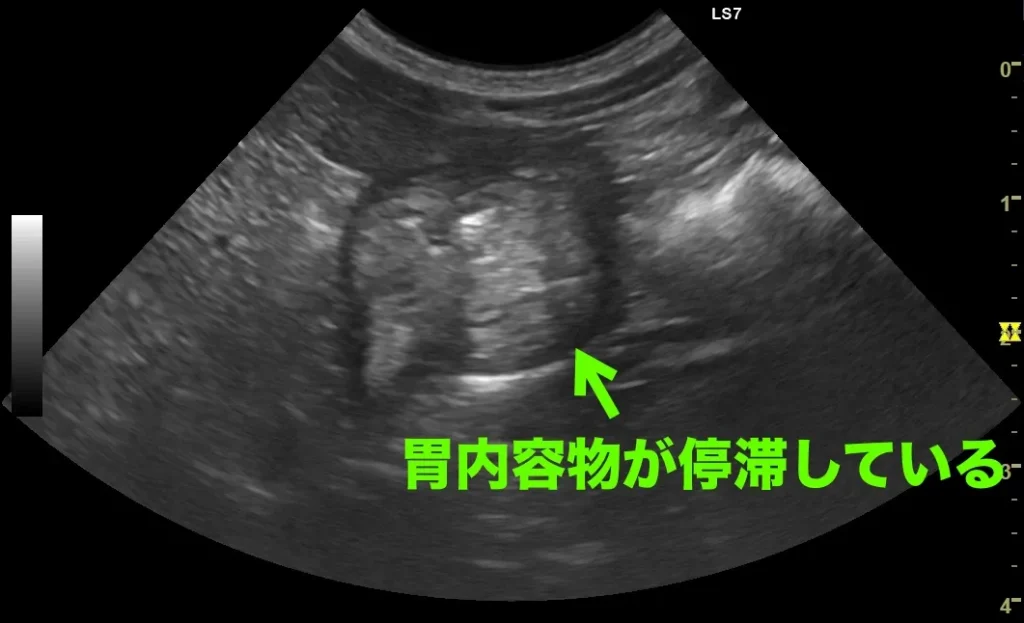

エコー検査で胃に軽度鬱滞所見あり

胃内異物の疑い